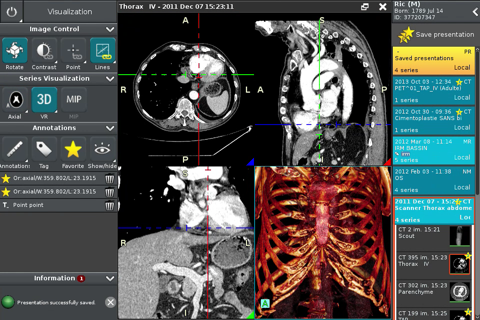

Anywhere Streaming is a DICOM visualization client that connects to Anywhere Server. It provide standard medical image navigation tools surch as : slicing, windowing, MPR, 3D VR, MIP, oblique ... All standard medical image modalities are ...